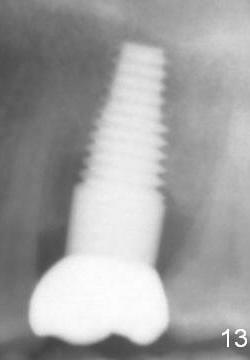

Bone appears to regenerate in the apical aspect of the mesial gap 5.5 months postop (Fig.12 <). The implant remains stable and is ready for restoration. The peri-implant radiolucency continues to reduce 1 year post cementation (Fig.13).